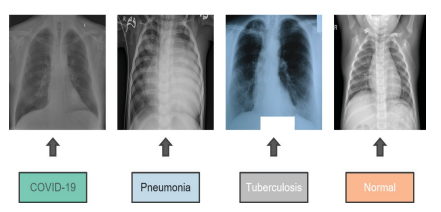

최종적으로 Covid19 / 폐렴 / 결핵 / 일반 4개 클래스로 구성된 최종 데이터 집합이 생성된다. 본 논문에서는 특정 사진 수정, 3채널 컬러 사진 적용, RGB 태그 지정 등의 전처리를 진행하여 보다 고품질, 고화질의 이미지로 훈련시켰다. 또한 2번 뒤집기, 셔플, 크기 조정, 이미지 모드의 범주형 변환 등의 변경절차도 진행하였다.